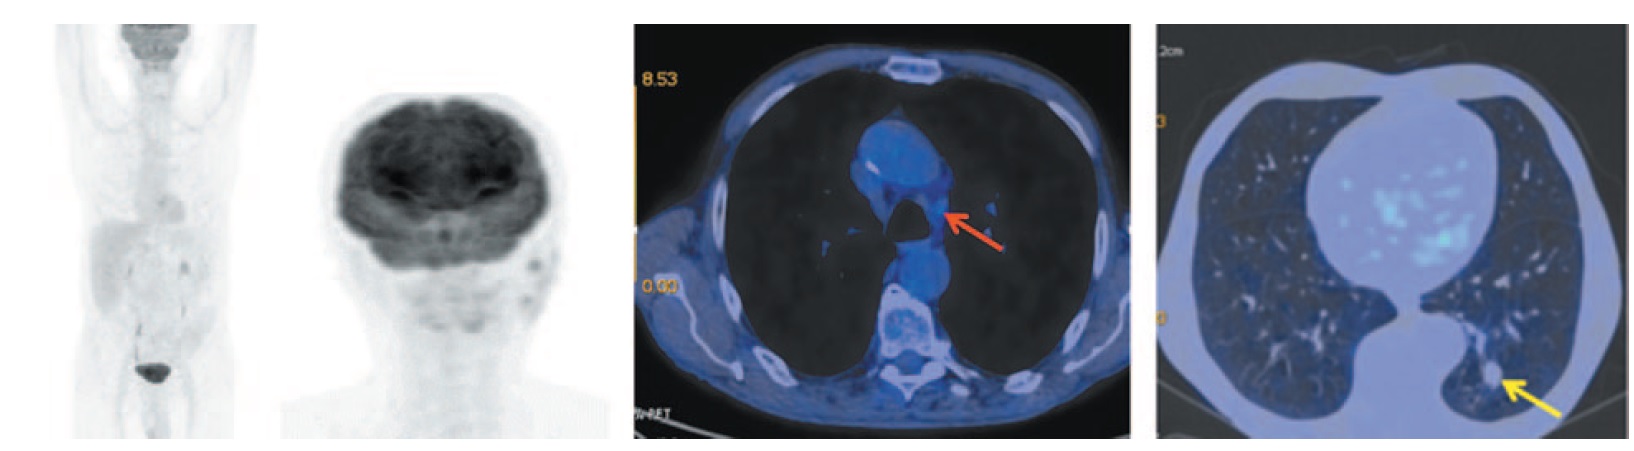

Комбинированная позитронно-эмиссионная и рентгеновская КТ (ПЭТ/КТ) с 18F-фтордезоксиглюкозой (ФДГ): патологическое образование в нижней доле левого легкого S10 размером 41×57×81 мм, SUVmax 10,75. В надключичной области справа определяется увеличенный метаболически активный лимфоузел размером до 14×9 мм, SUVmax 7,82. Увеличены паратрахеальные, бифуркационные, бронхопульмональные лимфоузлы (SUVmax 11,20), лимфоузлы аортопульмонального окна размером до 21×45 мм, SUVmax 10,53. В головном мозге в режиме рентгеновской КТ очаговых образований не выявлено. Экссудативный плеврит слева (рис. 1).

Рис. 1. Больной П., 76 лет, до лечения. На МIP- и аксиальных ПЭТ/КТ-проекциях определяется увеличенный метаболически активный надключичный лимфоузел справа размером до 14×9 мм, SUVmax 7,82. На фоне ателектаза нижней доли левого легкого в S10 визуализируется объемное образование (желтая стрелка), распространяющееся к корню, общим размером до 41×57×81 мм, прилегающее к задней костальной и паравертебральной плевре, с повышенной метаболической активностью ФДГ (SUVmax 10,75). Увеличены паратрахеальные, бифуркационные, бронхопульмональные лимфоузлы (SUVmax 11,20), лимфоузлы аортопульмонального окна размером до 21×45 мм, SUVmax 10,53 (красная стрелка). / Fig. 1. A 76-year-old patient P. before the treatment. MIP and axial PET/CT images show an enlarged metabolically active right supraclavicular lymph node measuring 14×9 mm, SUVmax 7.82. Against the background of atelectasis of the left lower lobe, a tumor mass formation (yellow arrow) is visualized in S10, extending to the root of the lung, with a total size measuring 41×57×81 mm, adjacent to the posterior costal and paraspinal pleura, with increased FDG metabolic activity (SUVmax 10.75). Enlarged paratracheal, bifurcation, bronchopulmonary lymph nodes (SUVmax 11.20) and aortopulmonary window lymph nodes measuring 21×45 mm, SUVmax 10.53 (red arrow) is detected.